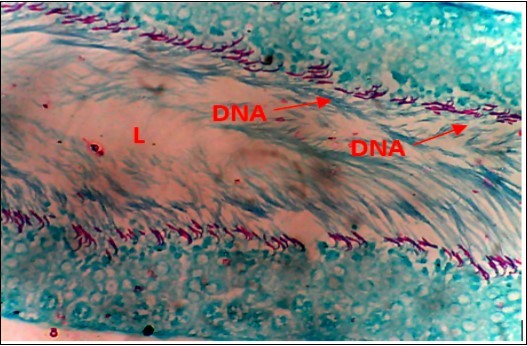

Local Nigerian men have been using AuriculariaPolytricha as a treatment for sexual dysfunction without supporting evidence from scientific experiments. This study was to investigate the effect of ethanolic extract of A. Polytricha on testicular DNA expression and some oxidative stress markers using STZ-Induced diabetic rats as a model. The experiment included six groups, Group A (Normal Control, treated with normal saline), Group B (treated with 65mg/kg.bw of STZ), Groups C, D, and E (treated with 250mg/kg.bw, 500mg/kg.bw, 1000mg/kg.bw AP after inducing diabetics), and Group F (treated with 40mg/kg.bw metformin after inducing diabetics). The experiment lasted for 35 days. After termination of the experiment, Fuelgen nuclear reaction was used for DNA demonstration to assess testicular DNA distribution while serum Superoxide Dimutase (SOD), Catalase and Melondialdehyde where evaluated using reagent based antioxidant enzyme assay. Results reveals that SOD and Melondialdehyde activities were remarkably (p<0.05) higher in diabetic control animals when compared with the normal control group. Values in Groups C, D and F that were administered with 250, 500mg/kg.bw A. polytricha and metformin respectively were also significantly (p<0.05) increased when compared with the normal control group. However, diabetic animals placed on 1000mg/kg.bw A. polytrichadid not show any statistical significance in comparison with normal control group but was remarkably (p<0.01) decreased when compared to the diabetic group that received low dose A. polytricha, an indication that the reversal is dose dependent. Catalase concentration in diabetic control animals was remarkably (p<0.05) higher when compared to the normal control but was not significantly (p<0.05) different in groups D (DM+500mg/kg.bw A. polytricha) and E (DM+1000mg/kg.bw A. polytricha) when compared with the normal control group. Diabetic control animals showed reduced magenta colour intensity of DNA and increased clustering and cross linking of DNA strands when compared with the normal control. However the degree of cross link in DNA strands was reduced in the diabetic animals placed on 1000mg/kg.bw A. polytrichawhen compared with the diabetic control group. Reversal in DNA damage and values of serum oxidative stress markers following administration of graded doses of A. polytricha could be attributed to essential phytochemical and therapeutic constituents in A. polytricha like polyphenol and flavonoid which can be found useful in prevention and treatment of diabetes induced testicular dysfunction. In summary, AP can contribute to a reversal in DNA damage and levels of serum oxidative stress markers in treating diabetes-induced testicular dysfunction.

Oxidative stress markers (SOD, catalase and Melondialdehyde) activities of different experimental animals. Figure 1, Figure 2. Results from Fuelgen DNA demonstration is shown in Figure 3, Figure 4, Figure 5, Figure 6, Figure 7, Figure 8.

Figure 4.Diabetic Control (DC) X400 – Section of testis showing scanty DNA stained with magenta colour. DNA strands are cross linked and appear in clusters

From findings in this study, irregular and distorted arrangements of DNA in all diabetic groups (Groups B, C, D, E and F) when compared with the normal control group, may have been due to displacement of sertoli cell within the germinal epithelium of seminiferous tubules. Strands of DNA were also seen arrange in clusters in diabetic groups, showing altered and defective structure which might have resulted from base free side deletion, frame shift, cross-linking and chromosomal rearrangement. The intensity of magenta colour development in Feulgen reaction for DNA demonstration was proportional to DNA concentration. There was reduced colour intensity in all diabetic groups (Groups B, C, D, E and F) when compared with the normal control. This is in line with report from Aitken and Krausz (2001). However the degree of distortion and cross-linking of DNA strand in the group of diabetic animal models placed on high dose (1000mg/kg.bw) of A. polytricha which may be a sign of amelioration. Groups C, D and F placed on 250mg/kg.bw A. polytricha, 500mg/kg.bw A. polytricha and standard anti-diabetic drug (metformin) respectively did not show remarkable differences in terms of DNA arrangements when compared with the diabetic control group. Groups D (500mg/kg.bw A. polytricha) and group E (1000mg/kg.bw) showed visible improvement in magenta colour intensity when compared with the diabetic control group.

Extensive experimental evidence 20, 21 have shown that ROS generated by diabetes is capable of modifying all bases, primarily guanine thereby altering the structure and producing defects by way of base free sites, deletion, shift in frame, DNA cross-link and chromosomal rearrangement. Agbaje et al., (2007) has documented that diabetic men are found to have a significantly higher percentage of spermatozoa and DNA damage and this was attributed to increased concentration of carboxymethyllysine (CML) and advanced glycation end (AGE) which are important triggers of oxidative stress in the reproductive tract of diabetic animals. DNA damage in this research may have resulted from increased generation of oxidative stress. Report from Mallidis et al., (2011) supports this findings.

The marginal reversal of DNA damage following 21 days of A. polytricha administration, as observed in this study may be linked to its polysaccharides constituent found to exhibit antimutagenic effect against in-vivo DNA damaging activities of indirectly acting alkylating agent. A. polytricha may have improved antioxidant status of experimental animals and was capable of ameliorating DNA damage which may be attributed to its potentials to regulate concentration of carboxymethyllysine (CML) and advanced glycation end (AGE) which are important triggers of oxidative stress in the reproductive tract of diabetic animals. AP is known to be a good exogenous source of antioxidant and may have ameliorated further DNA damage.